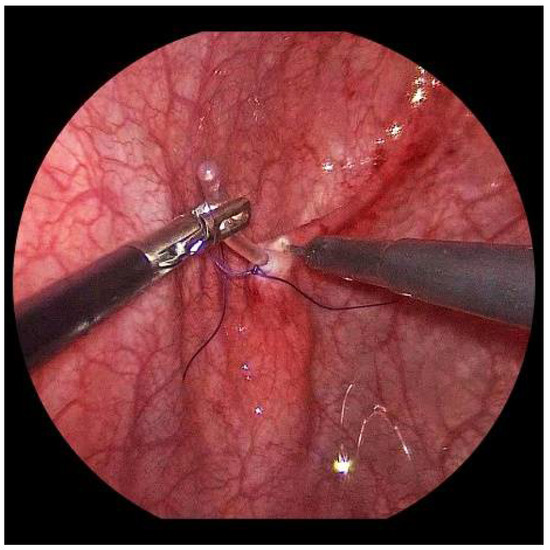

Submucosal tunnel preparation using curved scissors often requires some patience. When the tunnel is finished, the refluxive ureters are now shifted to the opposite side equivalent to the open approach. An ipsilateral suture fixes the ureter to the detrusor (Figure 6).

Figure 5. The submucosal tunnel is subtly prepared with curved scissors.